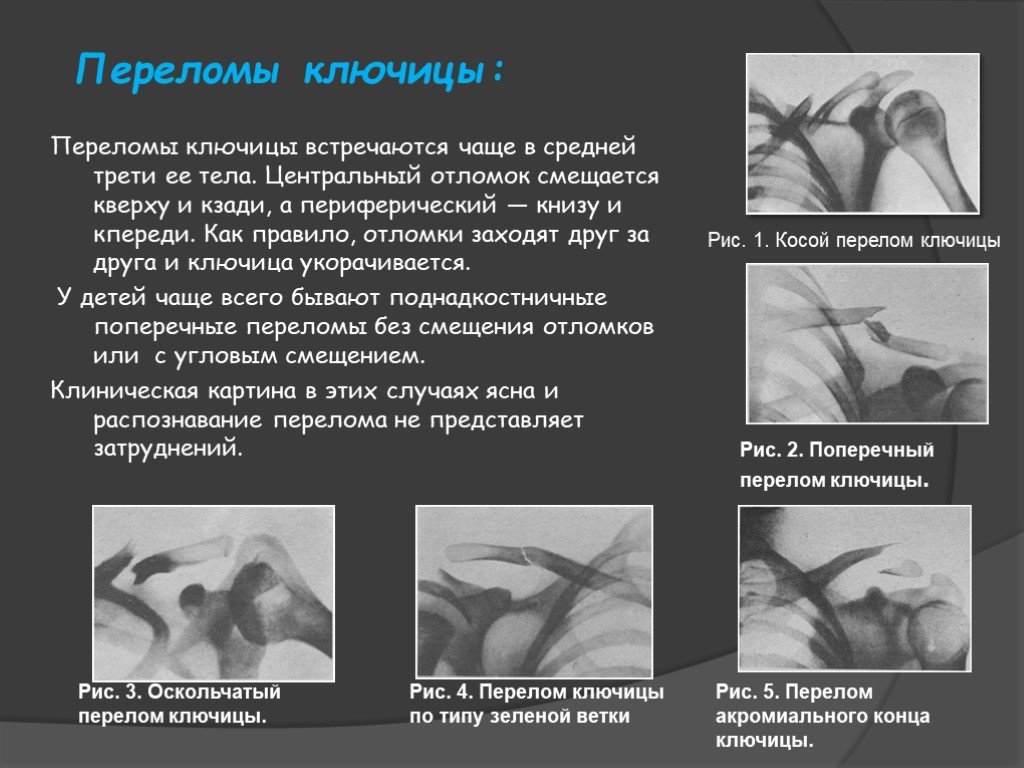

Вывихи и переломы ключицы презентация - 85 фото